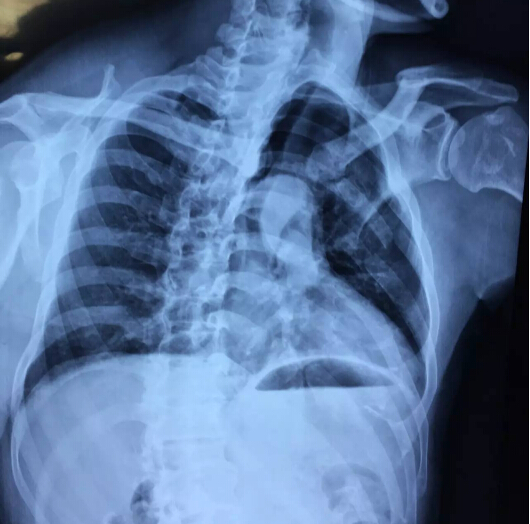

術(shù)前影像